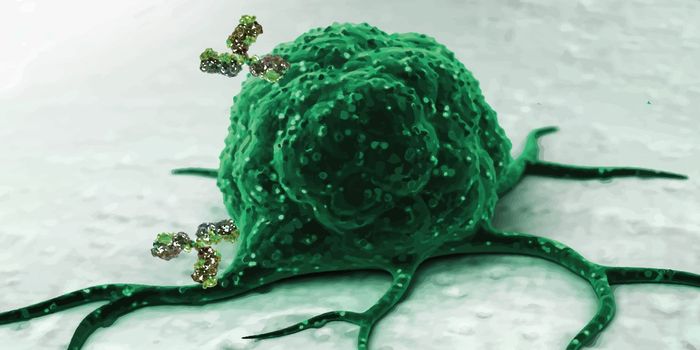

NOV 20, 2019ImmunologyManipulating the immune system’s population of natural killer cells could bolster therapies targeting cancer. A ne ...

JAN 23, 2018ImmunologyScientists propose extracting dendritic cells and priming them to fight cancer before returning them to a patient as par ...

DEC 10, 2015ImmunologySuperior technology brings us novel images of cancer cells and lymphocytes this week, and now scientists can learn more ...